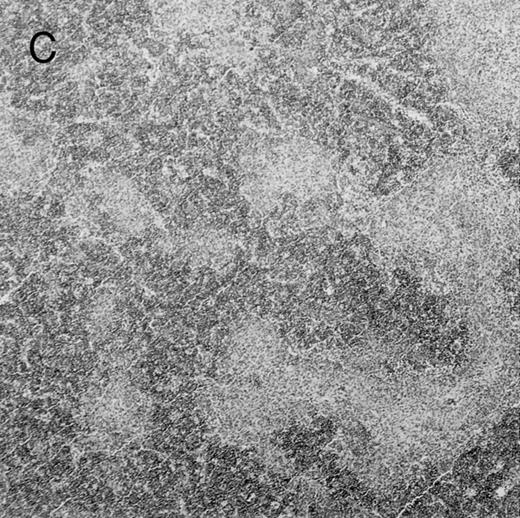

Histologic findings. Organs were collected at different times after BMT and tissue sections were stained with hematoxylin and eosin. Original magnifications for spleen (left) and liver (right) are ×40 and ×100, respectively. (A) B6 mice receiving FVB BM plus EpTK T cells. (B) Control group receiving BM only.

(C) B6 mice receiving FVB BM plus EpΔTK T cells and treated with GCV. (D) B6 mice receiving FVB BM plus EpΔTK T cells, treated with GCV, and developing a late onset GVHD (day 54).

FVB BM-grafted B6 mice: a model of lethal GVHD.We developed a model of GVHD resulting in 100% mortality soon after BMT using FVB mice, a strain not previously used as BM donors in experimental allogeneic BMT. We tested different combinations of recipient irradiation doses, as well as injected BM cell and CD3+ peripheral T-cell numbers. When 10-Gy–irradiated B6 mice were reconstituted with 107 FVB BM cells, we observed prolonged survival, whereas all ungrafted animals died before day 16 (Fig 2). In these conditions, more than 98% of splenocytes were of donor origin (Fig 3A). When 107 CD3+ peripheral T cells from mice of FVB genetic background were added to the FVB BMT, all animals died of GVHD between days 7 and 34 (Fig 2). Similar results were obtained using either PBS-treated mice receiving EpTK or EpΔTK peripheral T cells or GCV-treated mice receiving FVB nontransgenic peripheral T cells. Notably, this observation also indicates that both TK- and ΔTK-expressing T cells in the absence of GCV are fully competent to induce a lethal GVHD. Histopathologic examination of spleen and liver of these animals showed characteristic GVHD lesions such as (1) architecture disruption, necrosis, and congestion in the spleen; (2) hepatic periportal necrosis; (3) mononuclear portal infiltrates; and (4) endothelialitis of portal or centrolobular veinules (Fig 4A). By comparison, B6 mice receiving only FVB BM had a normal histology (Fig 4B).

Protection from GVHD was slightly less efficient in the group receiving EpΔTK CD3+ T cells. The survival rate was 79% at day 60 and 67% at day 120 (Fig 2B). However, two different outcomes must be distinguished. On the one hand, a majority of mice behaved as GCV-treated animals receiving EpTK T cells. They were apparently healthy, presented no skin lesions during a 120-day observation period, and showed complete donor-type hematologic reconstitution. There were no histological signs of GVHD in the spleen or liver (Fig 4C).

On the other hand, 5 of 19 mice exhibited signs suggesting the occurrence of a delayed GVHD (Table 1). Clinically, these animals presented weight loss and/or skin lesions on ears, neck, limbs, or abdomen, but only after day 40. In the absence of any further GCV treatment, 2 mice died 14 and 29 days after the occurrence of these signs (Table 1A) with histological signs of severe GVHD (Fig 4D). These results suggest that, in these mice, the 7-day GCV treatment was sufficient to prevent early, but not delayed GVHD.